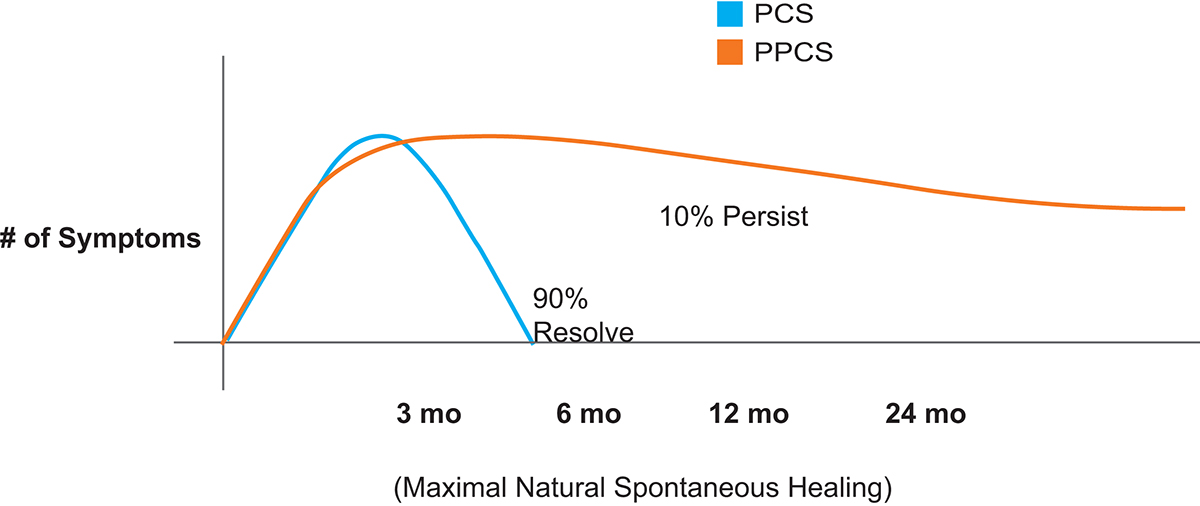

Following mTBI, individuals often experience symptoms of post-concussive syndrome (PCS). PCS symptoms include headache, dizziness, sleep disturbance, personality change, memory problems, attention and affective disturbances. 90% of mTBI PCS symptoms resolve completely. The 10% or so of patients with mTBI whose symptoms do not resolve within three to six months, develop persistent post-concussive syndrome (PPCS). (Fig 1)